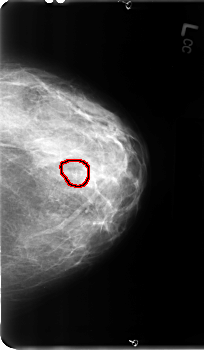

ics_version 1.0 filename B-3111-1 DATE_OF_STUDY 23 7 1996 PATIENT_AGE 44 FILM FILM_TYPE REGULAR DENSITY 3 DATE_DIGITIZED 22 1 1998 DIGITIZER LUMISYS LASER SEQUENCE LEFT_CC LINES 4888 PIXELS_PER_LINE 2856 BITS_PER_PIXEL 12 RESOLUTION 50 OVERLAY LEFT_MLO LINES 4864 PIXELS_PER_LINE 3040 BITS_PER_PIXEL 12 RESOLUTION 50 OVERLAY RIGHT_CC LINES 4792 PIXELS_PER_LINE 2880 BITS_PER_PIXEL 12 RESOLUTION 50 NON_OVERLAY RIGHT_MLO LINES 4824 PIXELS_PER_LINE 2960 BITS_PER_PIXEL 12 RESOLUTION 50 NON_OVERLAY |

FILE: B_3111_1.LEFT_CC.OVERLAY TOTAL_ABNORMALITIES 1 ABNORMALITY 1 LESION_TYPE CALCIFICATION TYPE PLEOMORPHIC DISTRIBUTION CLUSTERED ASSESSMENT 4 SUBTLETY 3 PATHOLOGY BENIGN TOTAL_OUTLINES 1 BOUNDARY |